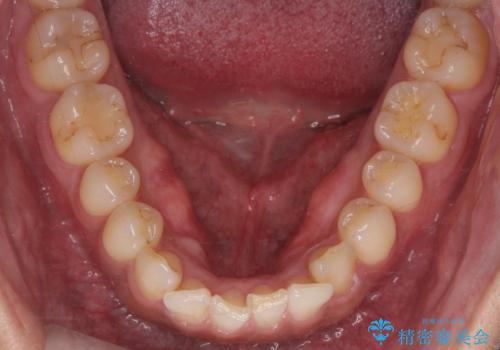

- 下顎の骨隆起を取りたいとのことで来院された患者様です。

右側と左側で2回に分けて行いました。